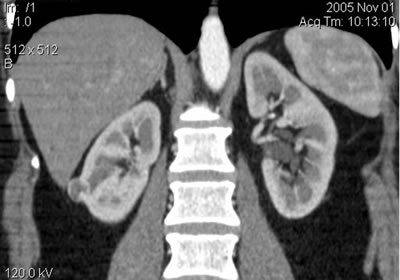

Медуллярная губчатая почка: диагностика с помощью КТ